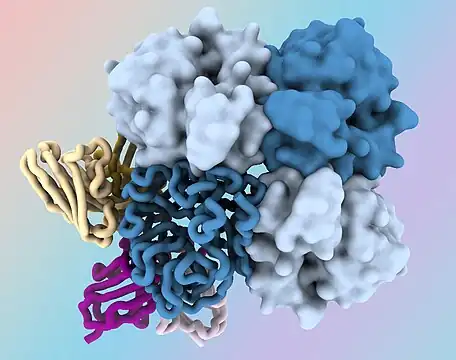

| Influenza virus, magnified approximately 100,000 times | |